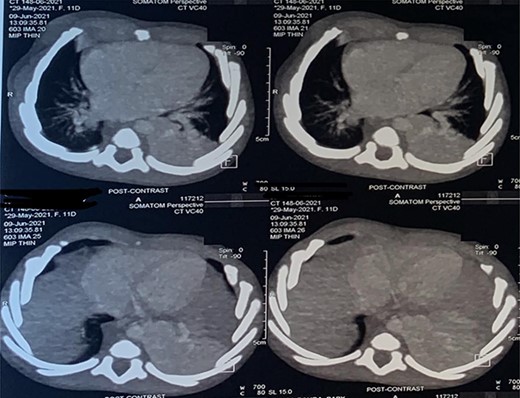

At surgery, the aberrant artery from the descending thoracic aorta (Fig. 3A) was dissected, isolated and doubly ligated with silk 1 and clips. A wedged resection of the sequestrated lung (Fig. 3B) was done, with Fig. 4 showing the normal lung after resection. No gastrointestinal tract communication was identified. A size 18F chest tube was left in situ after hemostasis. Patient was extubated on table and spent 2 days in the intensive care unit before being step down to the ward. The chest tube was removed on post-operative day 2 and he was discharged home on post-operative day 4 with subsequent follow-up on out-patient basis. He has been well with no complaints 6 months after surgery. Histopathologic evaluation of the resected sequestrated lung reported of thick-walled blood vessels in the lung parenchyma as well as evidence of hemorrhage and chronic inflammation within the alveolar spaces consistent with intralobar pulmonary sequestration.

(A) Blue arrow showing the anomalous artery from the descending thoracic aorta; (B) black arrow showing the erythematous and dense sequestrated lung.